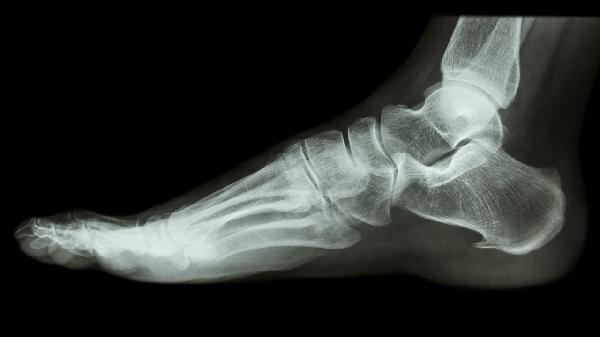

1、X线检查

X线检查是诊断跟骨舌型骨折的基础方法,能够清晰显示骨折线的位置和走向。通过正位、侧位及轴位投照,可观察跟骨的整体形态和骨折移位情况。X线检查操作简便且成本较低,适合作为初步筛查手段。但该检查对细微骨折或软组织损伤的显示效果有限。